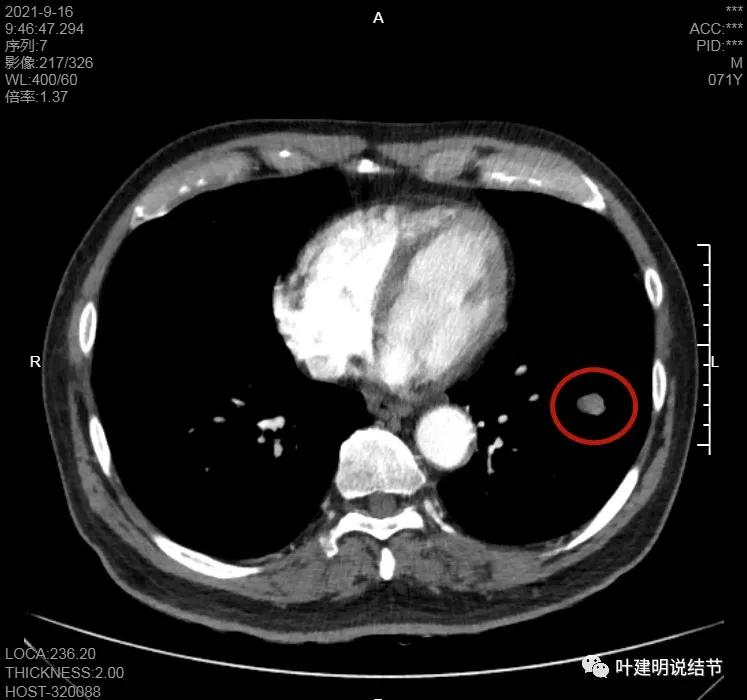

肿瘤筛查指标中的CEA与CA724高于正常。我们先来看其左下叶病灶的CT图像:

上图示病灶在左下叶,红色所指的与绿色箭头所指的是两个病灶,不相连的,实性结节

上图也示病灶是两个的,小的与大的之间有间隙的。大的病灶呈长方形似的